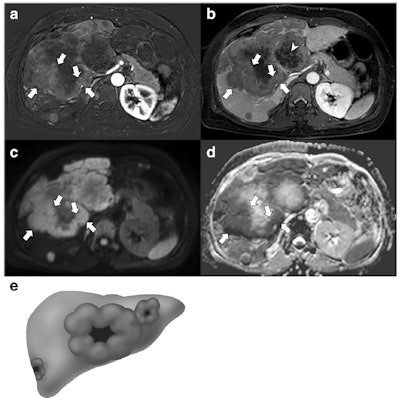

"Neuroendocrine tumors and their metastases to the liver and lymph nodes more frequently demonstrated a thick rim appearance on contrast-enhanced MRI and diffusion-weighted images," they reported. "The ratio of apparent diffusion coefficient values between the lesion and the spleen was significantly lower for the primary mass, liver metastases, and lymph node metastases of GB-NETs than for those of GB-ADCs. A large metastatic lymph node was the only poor prognostic factor for overall survival in patients with GB-NETs and GB-ADCs."

Of 63 patients, 21 had GB-NETs and 42 had GB-ADCs. Compared with GB-ADCs, GB-NETs more frequently demonstrated well-defined margins, intact overlying mucosa, and thick rim contrast enhancement and/or diffusion restriction on MRI scans. Liver metastases were more common and demonstrated thick rim contrast enhancement and diffusion restriction in GB-NETs, while lymph node metastasis showed thick rim diffusion restriction more often in GB-NETs than in GB-ADCs, the authors reported.

On quantitative analysis, the sizes of the gallbladder mass and metastatic lymph nodes in GB-NETs were larger than those in GB-ADCs (p = 0.002 and p = 0.010, respectively). The ratio of apparent diffusion coefficient values between the lesion and the spleen was lower in the gallbladder mass, liver metastases, and lymph node metastases of GB-NETs than those of GB-ADCs (p < 0.001, p = 0.017, and p < 0.001, respectively).

"We found that GB-NETs were significantly larger, frequently had a well-defined margin and intact overlying mucosa, and more often showed thick rim contrast enhancement and diffusion restriction, compared with GB-ADCs," the authors wrote. "In addition, liver and lymph node metastases were more common for GB-NETs, and these also demonstrated thick rim contrast enhancement and diffusion restriction."